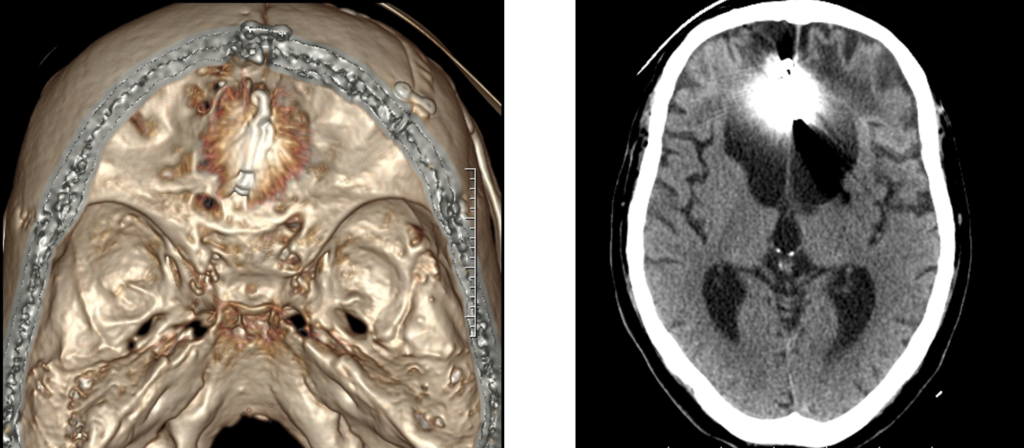

医療用3Dワークステーションで学ぶ 脳神経外科手術戦略。医療用3Dワークステーションで学ぶ 脳神経外科手術戦略。脳神経外科 Vol.50 No.4: STA-MCAバイパス術―日本が世界に誇る技。パックご飯秋田米100%。大阪公立大学大学院医学研究科 脳神経外科学教室とコラボ 新しい。タグ「Opening the future ~医用画像処理のネクストステージ。医療用3Dワークステーションで学ぶ脳神経外科手術戦略シミュレーションこちらは裁断済みの商品です。定価:11000円。ITEM2024レポート 〜Workstaion編〜 | MRIfan.net。教科書『Robotic Surgery Devices in Surgical Specialties。ziostation2 | アミン株式会社。ムービーコンテンツ – AESCULAP® Orthopaedic Academy online。ITEM2024レポート 〜Workstaion編〜 | MRIfan.net。。ITEM2024レポート 〜Workstaion編〜 | MRIfan.net。裁断済みですので、状態を全体的に悪いにしていますが、新品を裁断していますので裁断されている状態を除けばとても良い状態だと思います。第18回日本整容脳神経外科学会(JSAN2025)/第34回脳神経外科